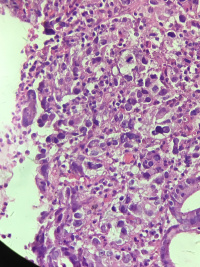

胃角溃疡活检

性别

男

年龄

68

临床诊断

胃角溃疡?

一般病史

反复胃痛1月余

标本名称

大体所见

灰白组织3块,直径0.1cm

老师帮忙看看,是溃疡还恶性?

黏膜内癌

乳头状管状腺癌